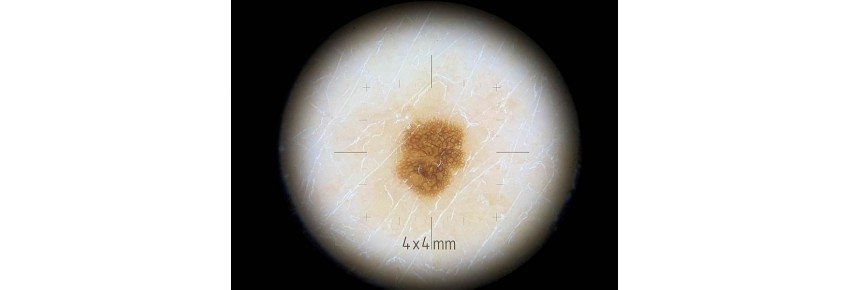

The adapter for difficult areas is an essential accessory for DermLite DL200HR and DL200HYBRID dermatoscopes, designed to enable accurate diagnosis even in the hardest-to-reach areas of the body. With its compact diameter of 10mm, this adapter ensures versatility and precision in dermatological examinations.

• Compact diameter of 10mm: ideal for examining hard-to-reach areas.

• Fine mesh 4x4 mm: allows for detailed skin analysis, even in the most complex areas.